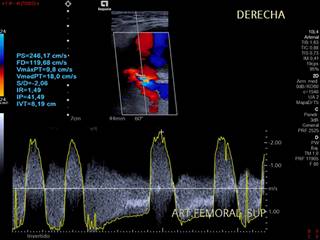

Hombre de 76 años con fibrilación auricular, a quien se le realiza coronariografía diagnóstica con abordaje femoral derecho. Después de ese evento en el postoperatorio se identifica evolución de lesión focal adyacente al sitio de punción, la cual era dolorosa e incrementaba su volumen e induración de forma diaria, por lo que se solicita ultrasonido Doppler de miembro inferior derecho para su valoración encontrándose pseudoaneurisma de la arteria femoral derecha (Figuras 1 y 2).

Figura 1: Doppler espectral del sitio de comunicación del pseudoaneurisma en donde se visualiza fenómeno de aliasing, espectro bifásico equidistante, velocidad picosistólica e índice de resistencia elevado.

El diagnóstico de un pseudoaneurisma se debe realizar con ultrasonido Doppler, dentro del cual las características a buscar son la imagen en “Ying Yang”, velocidad picosistólica e índice de resistencia altos, tamaño, dependencia arterial específica y tamaño del cuello aneurismático. Se puede realizar tomografía o resonancia magnética complementaria en caso de requerirse para acompañar su valoración en términos de extensión en casos complejos.2